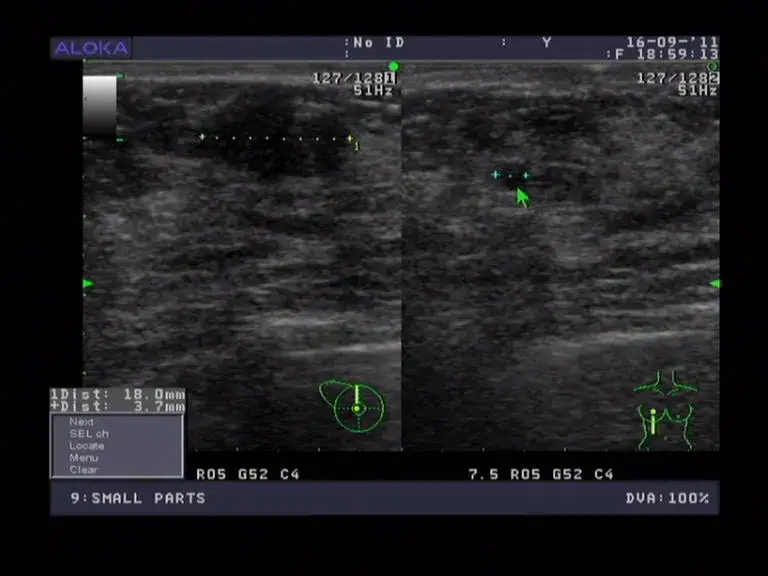

Następnie lekarz przesuwa głowicę ultradźwiękową po powierzchni piersi. Fale dźwiękowe emitowane przez urządzenie tworzą obraz wnętrza piersi, co pozwala na zidentyfikowanie ewentualnych nieprawidłowości. Cały proces jest bezbolesny, a pacjentka może czuć jedynie chłód żelu oraz delikatny nacisk głowicy.

Ważne jest, aby zrozumieć, co oznaczają wyniki badania. Wyniki USG piersi są zazwyczaj przedstawiane w formie opisu oraz obrazów, które pokazują stan tkanek. Pacjentka powinna omówić wyniki z lekarzem, aby uzyskać pełne zrozumienie sytuacji zdrowotnej oraz ewentualnych kroków, które należy podjąć w przyszłości.